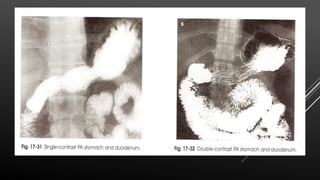

Barium –PA stomach, single contrast study

Barium meal- single contrast

Demonstration of rugal folds